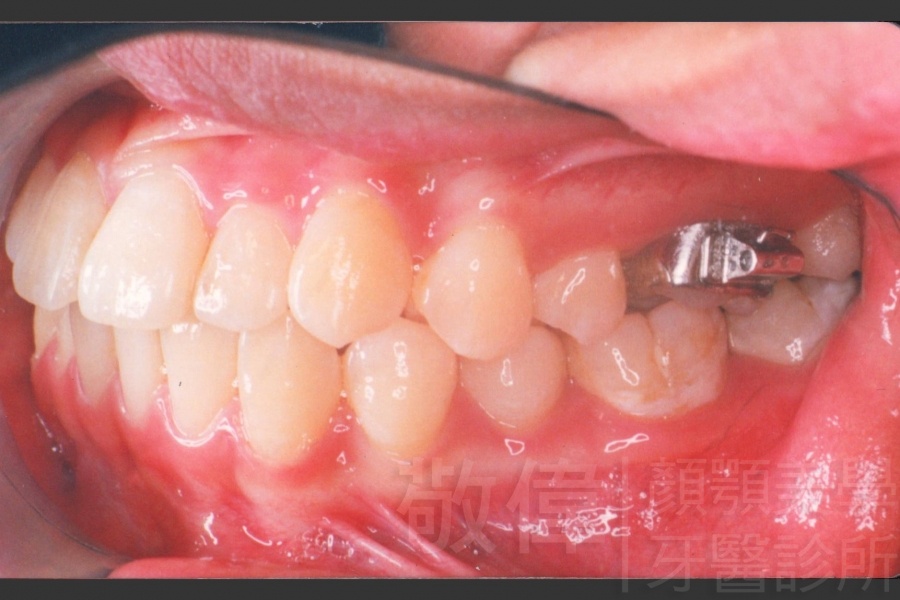

變臉矯正,原來戽斗妹跟大歪臉變成自信正妹

經由本院3D數影X光影像儀分析、與3D齒顎顏矯正技術,再配合口腔顎面正顎專科醫師施以正顎手術治療,雙方共同合作,使患者臉部外觀有很好的改善,大歪變小歪,產生了天南地北的大改變,她的人生也整個變得不一樣。

因為矯正與正顎手術的配合,使「戽斗妹」變成了「陽光正妹」,完全的改變了她的人生,在面對各種場合、與人交際都散發出自信微笑。所以,奉勸家長,如果小朋友有臉顎畸型的問題,應該考慮配合做這種簡單、安全、有效的正顎手術。